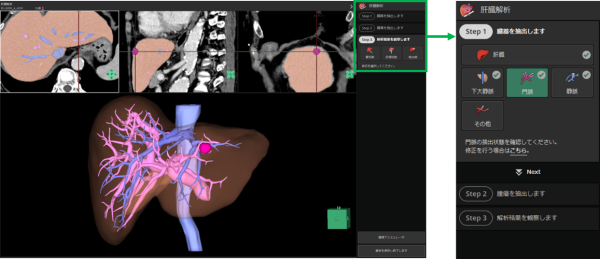

+肝臓変形機能

肝臓の術前シミュレーションを支援する「肝臓解析」と組み合わせて使用する「+肝臓変形機能」は、肝臓の3D画像に対して肝臓および周辺臓器を変形させながら観察することができる。術前に肝臓を切除する術式のシミュレーションを直観的な操作で行うことが可能で、手術時に切除する際の各脈管の位置推定をサポートする。

術前シミュレーションを支援する「肝臓解析」や「膵臓解析」など8つの解析機能をシンプルかつ直観的に操作できる「Quickモード」に切り替えて使用できる。従来のユーザーインターフェースでの操作と比較して簡便かつ迅速に解析を行うことができる。